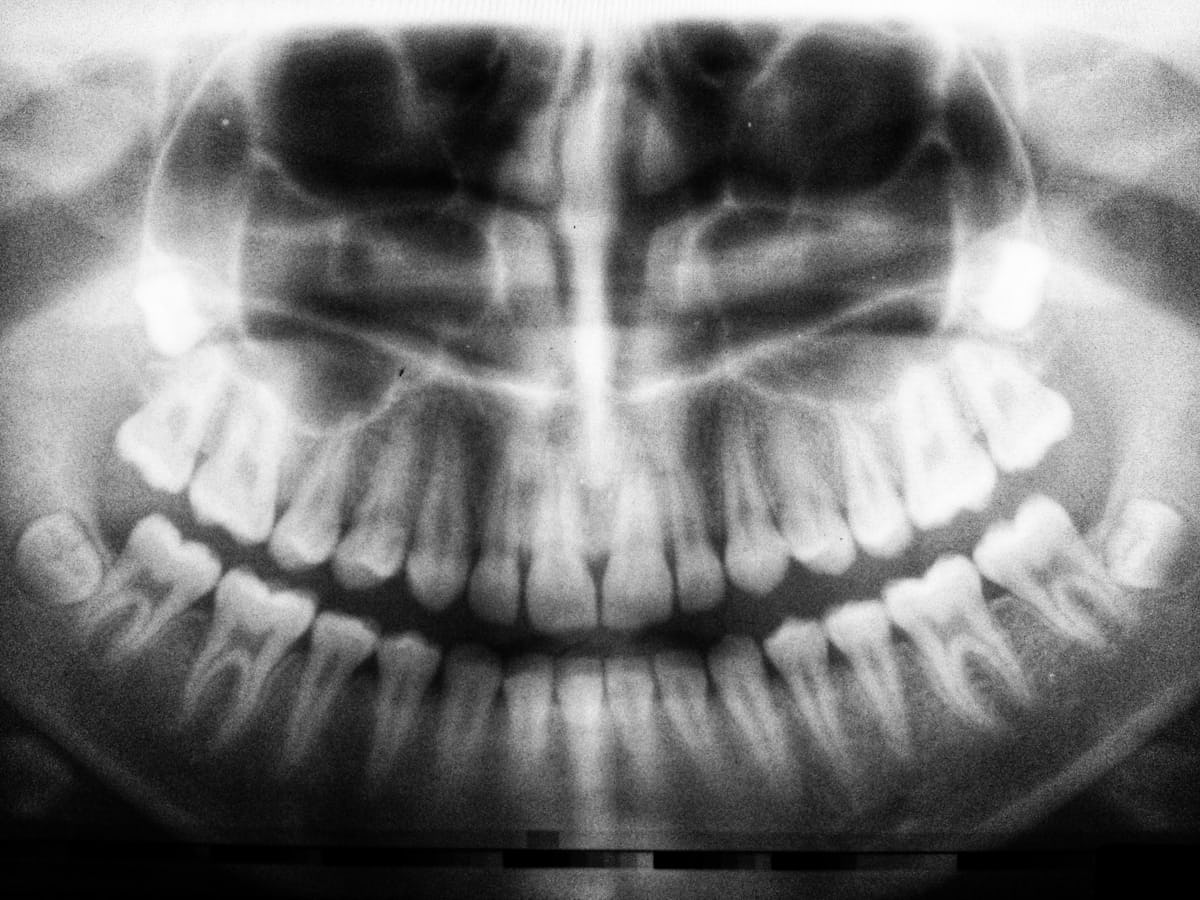

Root canal therapy — sometimes simply called a root canal — is a dental procedure that treats infection or damage deep inside a tooth. Every tooth contains a soft inner tissue called the pulp, which is made up of nerves, blood vessels, and connective tissue. The pulp sits within narrow channels called root canals that extend from the centre of the tooth down through the roots and into the jawbone.

When the pulp becomes inflamed or infected due to deep decay, a crack or fracture, repeated dental procedures on the same tooth, or an injury, it can cause significant pain and lead to a dental abscess if left untreated. Root canal therapy removes the infected or damaged pulp, cleans and disinfects the inside of the tooth, fills and seals the canals to prevent reinfection, and preserves the natural tooth so it can continue to function normally.

Many patients are unsure whether their symptoms point to a root canal or something less serious. While only a proper examination and X-ray can confirm the diagnosis, there are several common warning signs to be aware of.